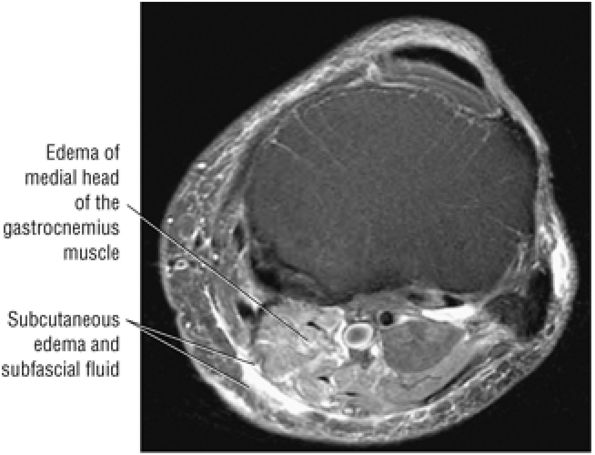

Thickening (Fig. 5.180) or absence of the ligament in acute injury

-

Subacute to chronic residual thickening in a healed and scarred ligament (Fig. 5.181)

Chronic instability associated with attenuated or hypoplastic ligament with sharper, more defined ligament margins